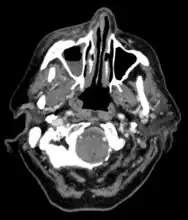

Imaging

Imaging is often performed, such as CT scan of lungs and sinuses.[38] Signs on chest CT scans, such as nodules, cavities, halo signs, pleural effusion and wedge-shaped shadows, showing invasion of blood vessels may suggest a fungal infection, but does not confirm mucormycosis.[16] A reverse halo sign in a person with a blood cancer and low neutrophil count, is highly suggestive of mucormycosis.[16] CT scan images of mucormycosis can be useful to distinguish mucormycosis of the orbit and cellulitis of the orbit, but imaging may look identical to those of aspergillosis.[16] MRI may also be useful.[39]

CT head (axial): invasion of right maxillary sinus (presented with double vision, swollen painful eye).